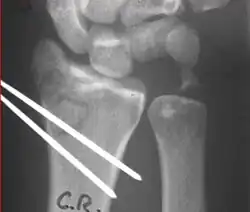

Closed reduction of a distal radius fracture involves first anesthetizing the affected area with a hematoma block, intravenous regional anesthesia (Bier's block), sedation or a general anesthesia.[5] Manipulation generally includes first placing the arm under traction and unlocking the fragments. The deformity is then reduced with appropriate closed manipulative (depending on the type of deformity) reduction, after which a splint or cast is placed and an X-ray is taken to ensure that the reduction was successful. The cast is usually maintained for about 6 weeks.[5]

Surgical options have been shown to be successful in patients with unstable extra-articular or minimal articular distal radius fractures. These options include percutaneous pinning, external fixation, and ORIF using plating. Patients with low functional demand of their wrists can be treated successfully with nonsurgical management; however, in more active and fit patients with fractures that are reducible by closed means, nonbridging external fixation is preferred, as it has less serious complications when compared to other surgical options.[5] The most common complication associated with nonbridging external fixation is pin tract infection, which can be managed with antibiotics and frequent dressing changes, and rarely results in reoperation.[5] The external fixator is placed for 5 to 6 weeks and can be removed in an outpatient setting.[5]